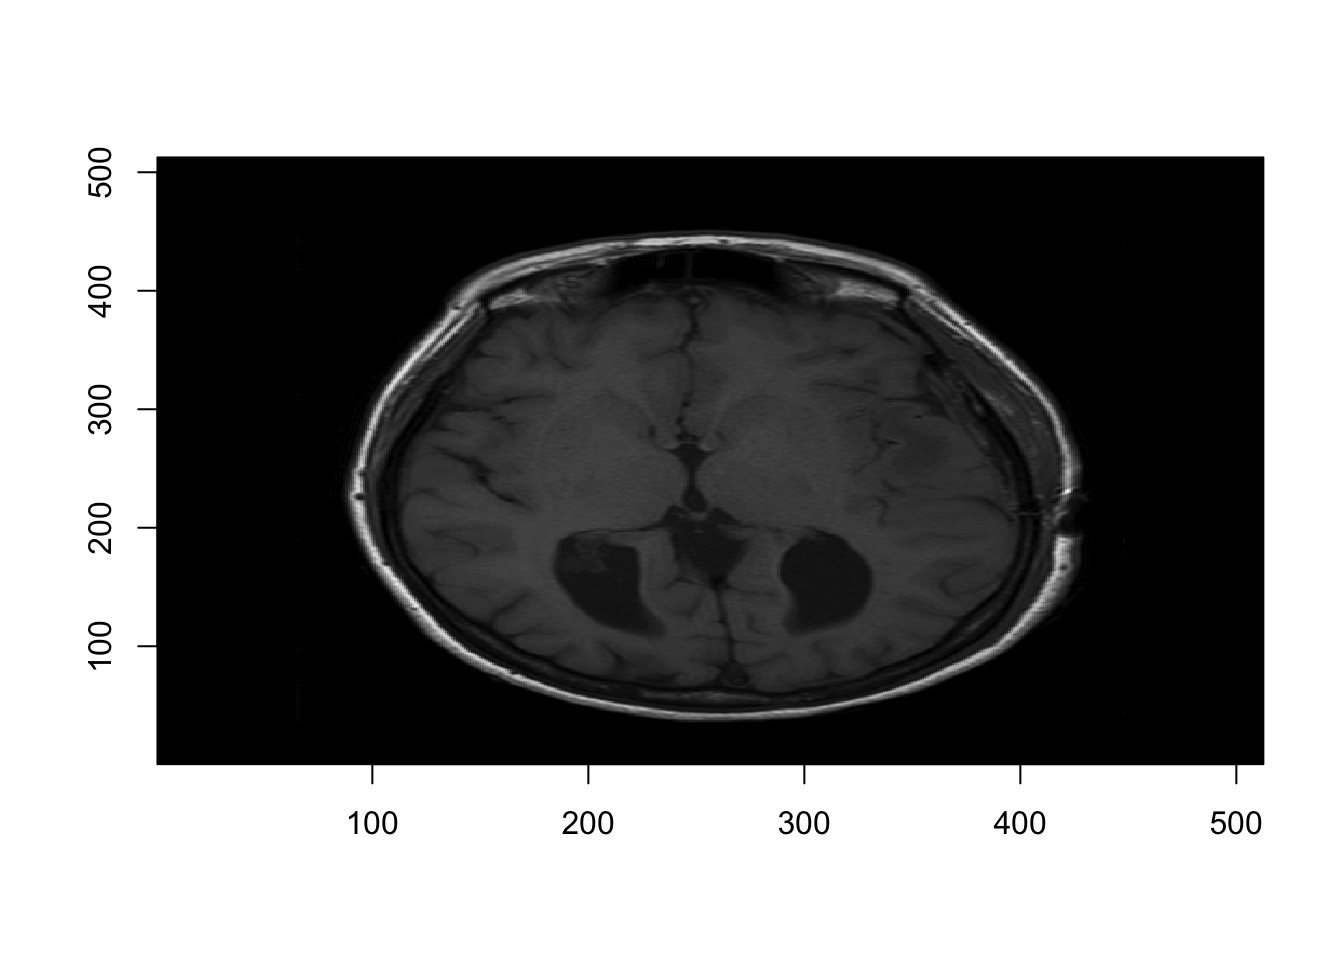

And plot one slice: